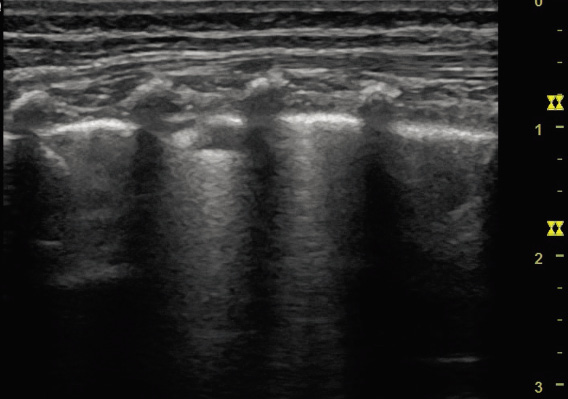

Bronquiolitis

• Patrones ecográficos:

– Aumento de líneas B difusas, múltiples/coalescentes: los septos interlobulillares subpleurales engrosados por el edema producen la reverberación de los haces de ultrasonido que forman las líneas B. Un aumento en el número de líneas B (más de tres líneas B por cada espacio intercostal) indica un aumento del edema y de la congestión. Cuando hay un aumento del líquido interlobulillar importante, las líneas B se fusionan, produciendo el llamado patrón de pulmón blanco pulmonar.

– Engrosamiento o irregularidad pleural: tanto por el edema alveolar como por la disminución de la aireación pulmonar, la línea pleural suele ser irregular, engrosada o mal definida.

– Pequeñas consolidaciones subpleurales: las áreas de hipoventilación pulmonar con ausencia de aire alveolar se visualizan en forma de consolidaciones adyacentes a la línea pleural (Fig. 8).

Figura 8. Patrones ecográficos en bronquiolitis. A. Aumento de líneas B difusas, múltiples/coalescentes. B. Engrosamiento o irregularidad pleural. C. Pequeñas consolidaciones subpleurales (flecha).

En la bronquiolitis es típica la afectación bilateral y heterogénea, que alterna áreas de pulmón patológico con áreas de pulmón sanas, que lo diferencia de otras entidades que también pueden presentar un síndrome intersticial, como son el edema cardiogénico, la neumonía intersticial o el síndrome de distrés respiratorio agudo.